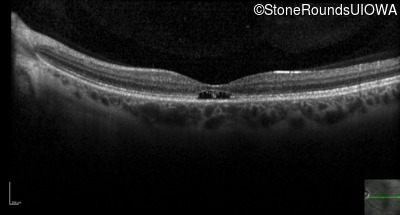

Optical Coherence Tomography - Right - 20/20 -1

Exemplar / OCT Stack